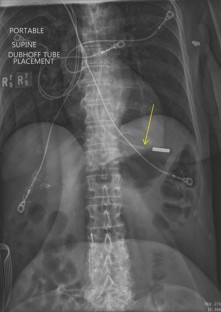

Fig. 2